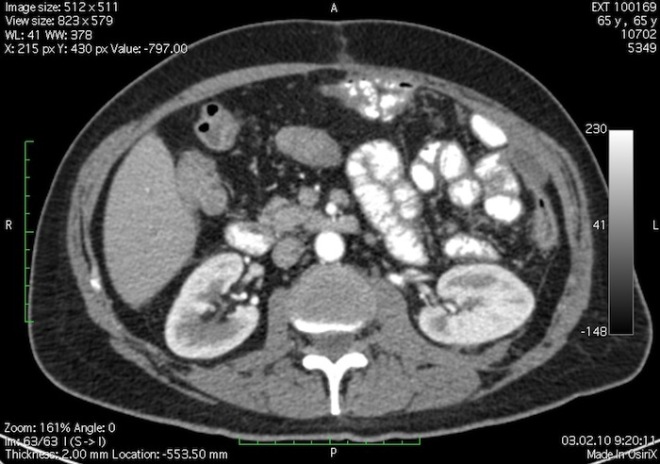

В компьютерной томографии (КТ) используются рентгеновские лучи. Веерообразный пучок движется вокруг тела, сканируя его с разных сторон. Круговая система детекторов фиксирует разницу ослабления рентгеновского излучения после прохождения через ткани, обрабатывает данные компьютером. Современные аппараты проводят обследование точно и быстро, снижая дозу облучения до минимума.

Врачи отмечают, что выбор между КТ и МРТ почек зависит от конкретной клинической ситуации и целей диагностики. Компьютерная томография позволяет быстро получить детализированные изображения, что особенно полезно в экстренных случаях, например, при подозрении на камни в почках или травмы. КТ также хорошо визуализирует костные структуры и может выявить опухоли. Однако этот метод связан с облучением, что ограничивает его использование у некоторых пациентов.

Разница в информативности КТ и МРТ состоит в том, что МРТ определяет даже незначительные изменения в почечной паренхиме и выявляет опухоли почек на самых ранних стадиях, а КТ , метод, позволяющий лучше визуализировать камни при мочекаменной болезни, что важно для предстоящей операции по их удалению или дроблению.

Доза облучения при КТ за время одного обследования внутренних органов в зависимости от используемого оборудования и времени исследования составляет 6-9 мЗв. Она немного возрастает при применении контрастных веществ на основе йодина и бария. Предельно допустимых доз облучения пациентов во время диагностики не установлено. Но если была лучевая нагрузка, полученная при ранее проведенных рентгеновских обследованиях, нужно проинформировать об этом своего врача.

Риск от облучения не должен превышать риск отказа от его проведения. Допустимый интервал между двумя процедурами КТ 2-3 месяца, но лучше, если он составит полгода.